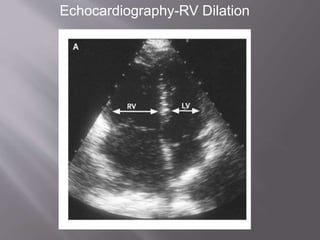

 RV dilation

 RV/LV short axis >1= pulmonary

hypertension

 RV/LV short axis >1.5= severe PE

 Leftward septal bowing

Echocardiography-RV Dilation

Arch Intern Med. 2005;165:1777-1781

 RV dilation RV/LV short axis >1= pulmonary hypertension  RV/LV short axis >1.5= severe PE  Leftward septal bowing

Arch Intern Med.2005;165:1777-1781